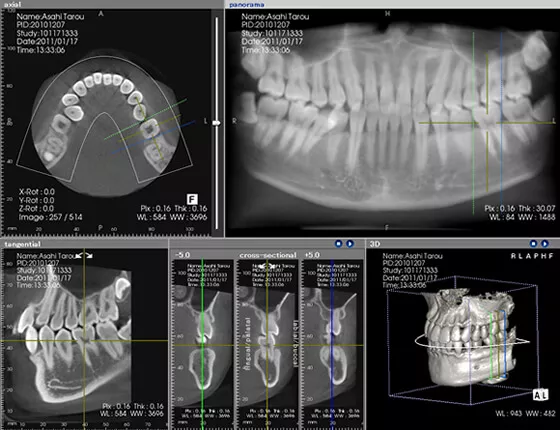

CTは立体的に撮影できる装置で、平面でのレントゲンと比べ、「見える」精度が異なります。例えば、顎の構造や血管、神経の位置などが立体的に把握でき、問題箇所の見落としも少なくなります。